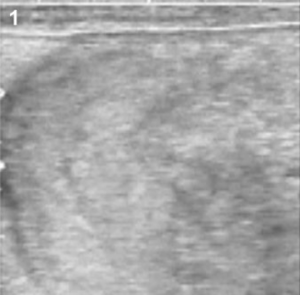

The exploration of the uterus in the non-pregnant female aims to either determine the stage of the oestrous the uterus (Beal et al., 1992). The histology of the uterus determines its echogenicity as the submucosa can be visualized as an anechoic layer beneath the endometrium. During the follicular phase, under the influence of oestrogens, the blood vessels in the submucosa become hyperaemic, the endometrium becomes oedematous, increasing its thickness, and the anechoic vascular zone is more easily visualized. The content of the uterine lumen may also vary during the oestrous cycle, being typically absent during the luteal phase, whereas a small amount of fluid may be present during the follicular phase (Barlund et al., 2008). Apart from the oestrus phase various pathologies and pregnancy status can also be visualised through ultrasonography (Fig: 5)

Fig 5: Different stages of uterus and ovaries (Quintela et al., 2012)